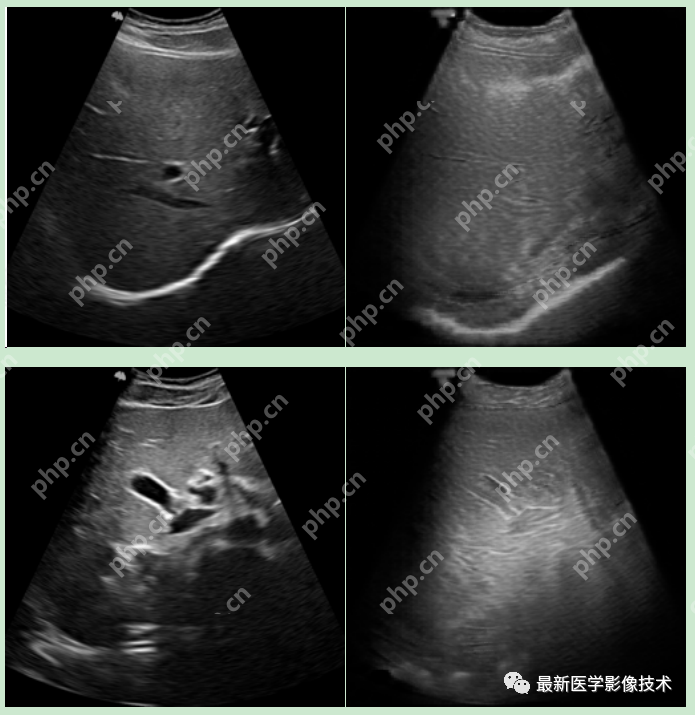

5、验证集部分生成结果

左图为低质量图像,中间为生成的高质量图像,右图为真实的高质量图像。